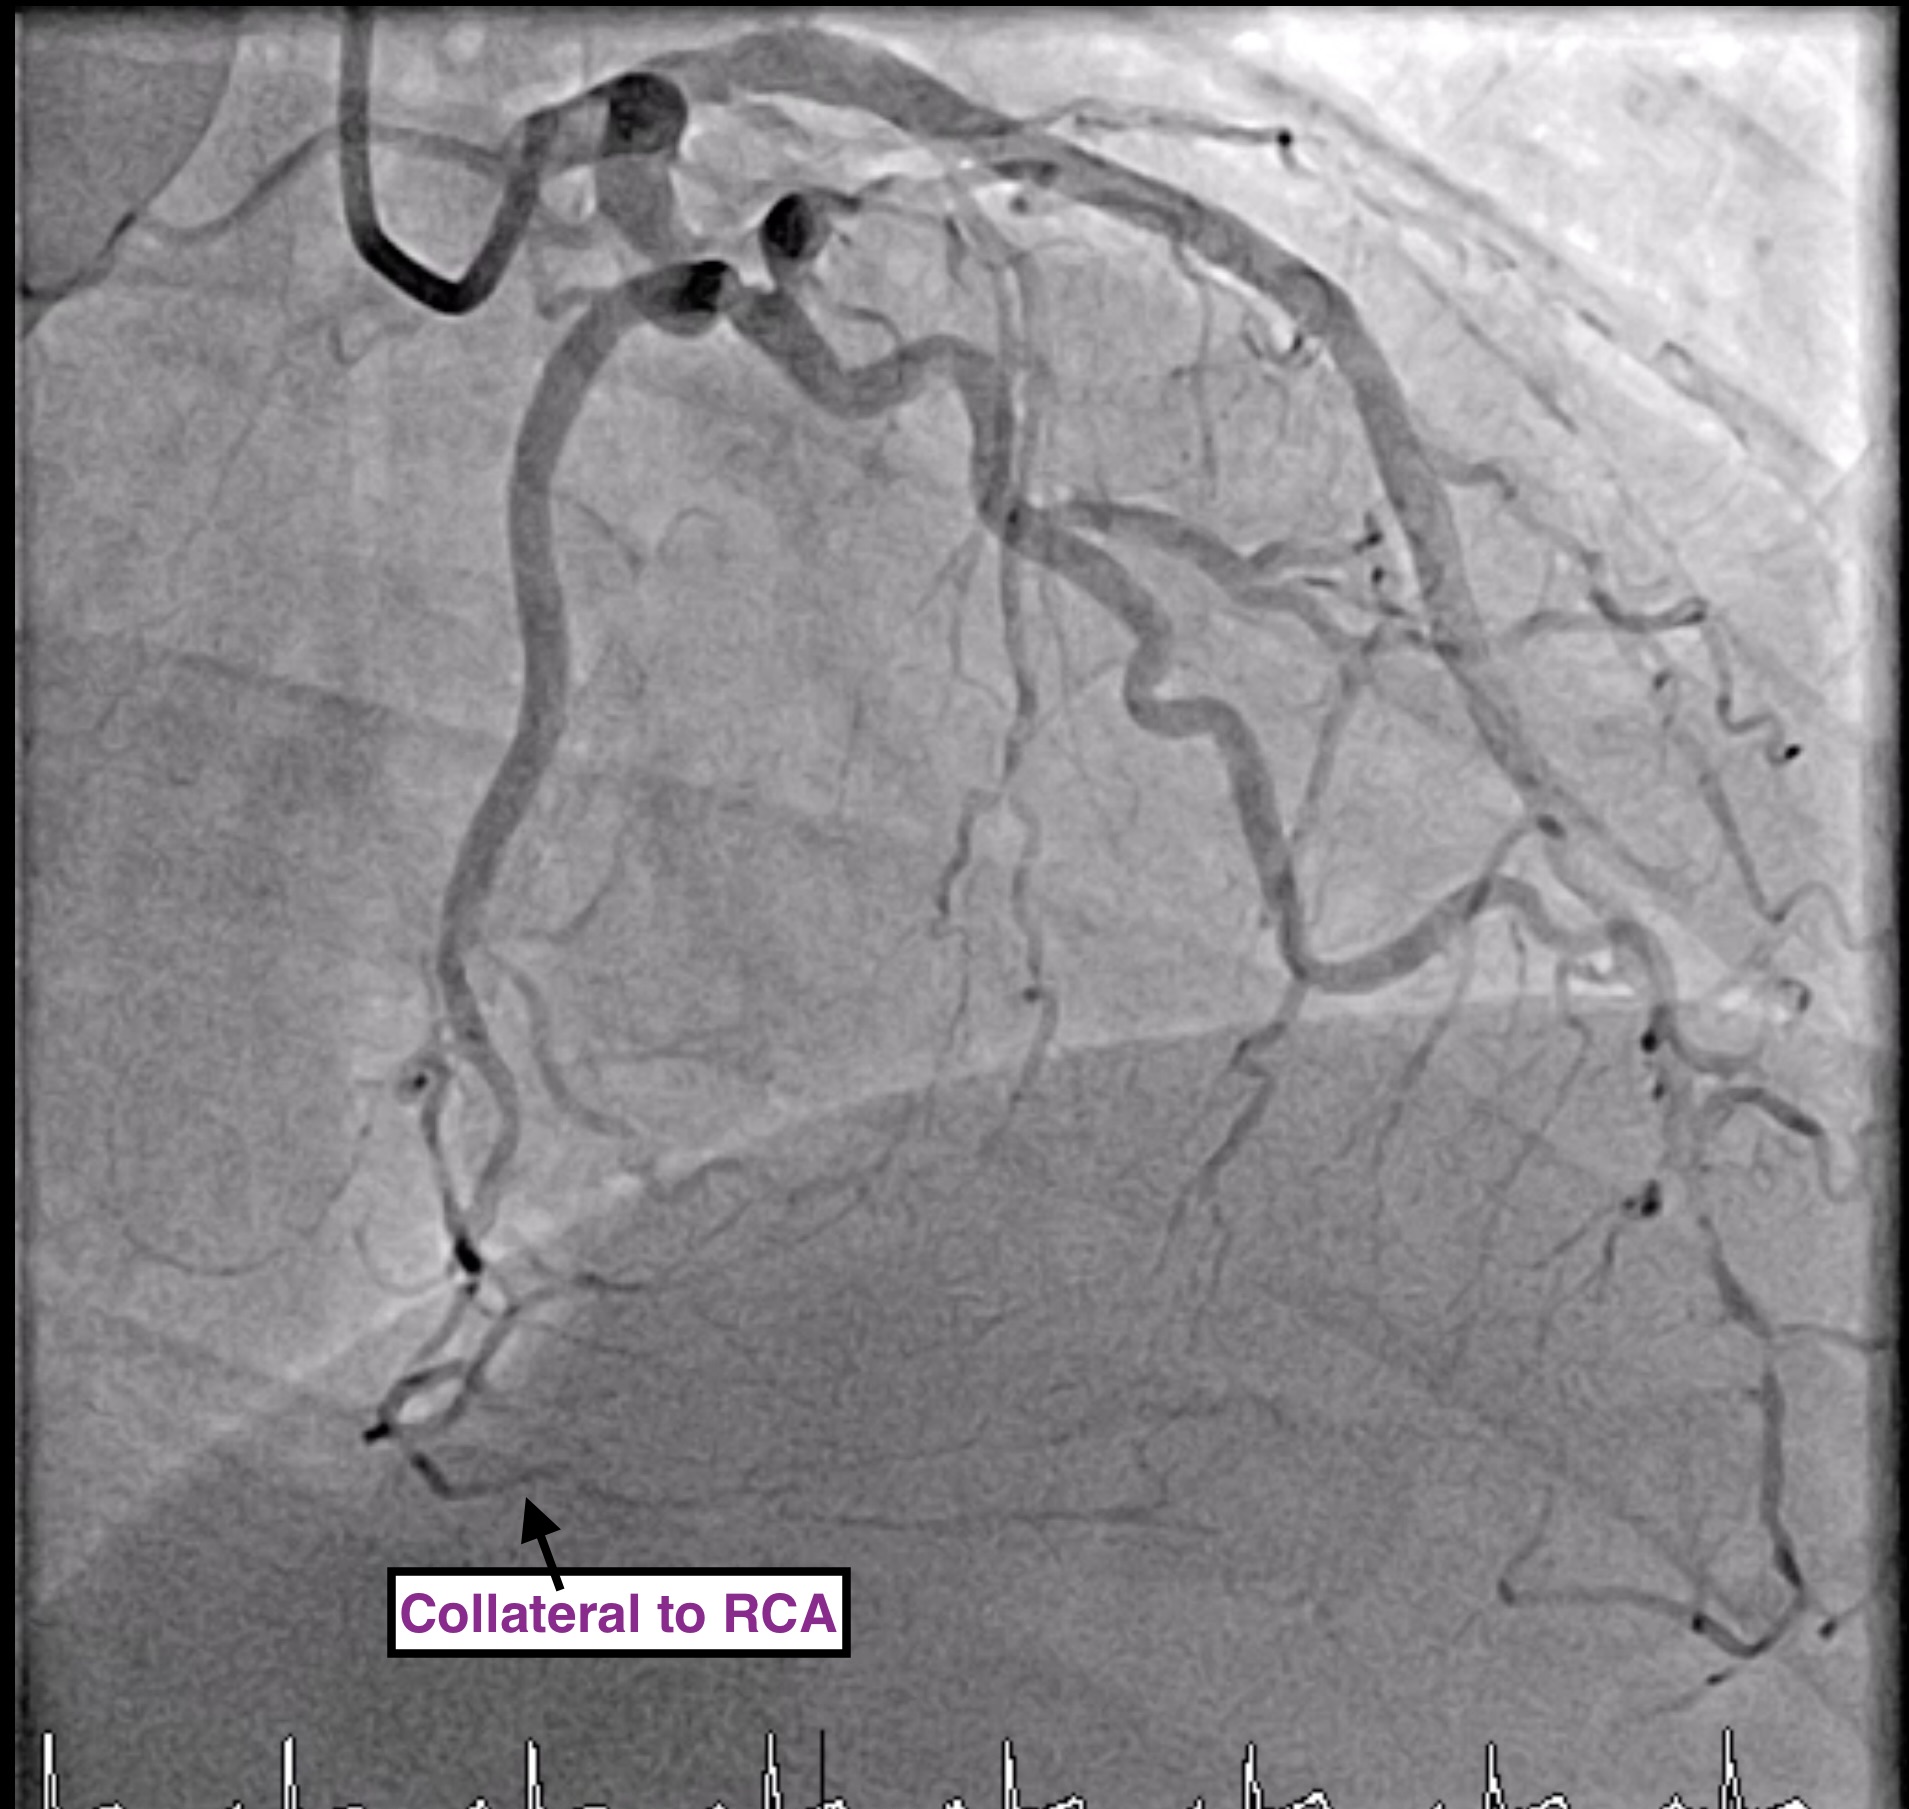

LM: NormalLAD: Patent proximal to mid-LAD stentLCx: No significant stenosisRCA: Patent stent at proximal RCA, CTO mid to distal RCA, receive collateral to PL and PDA from LAD